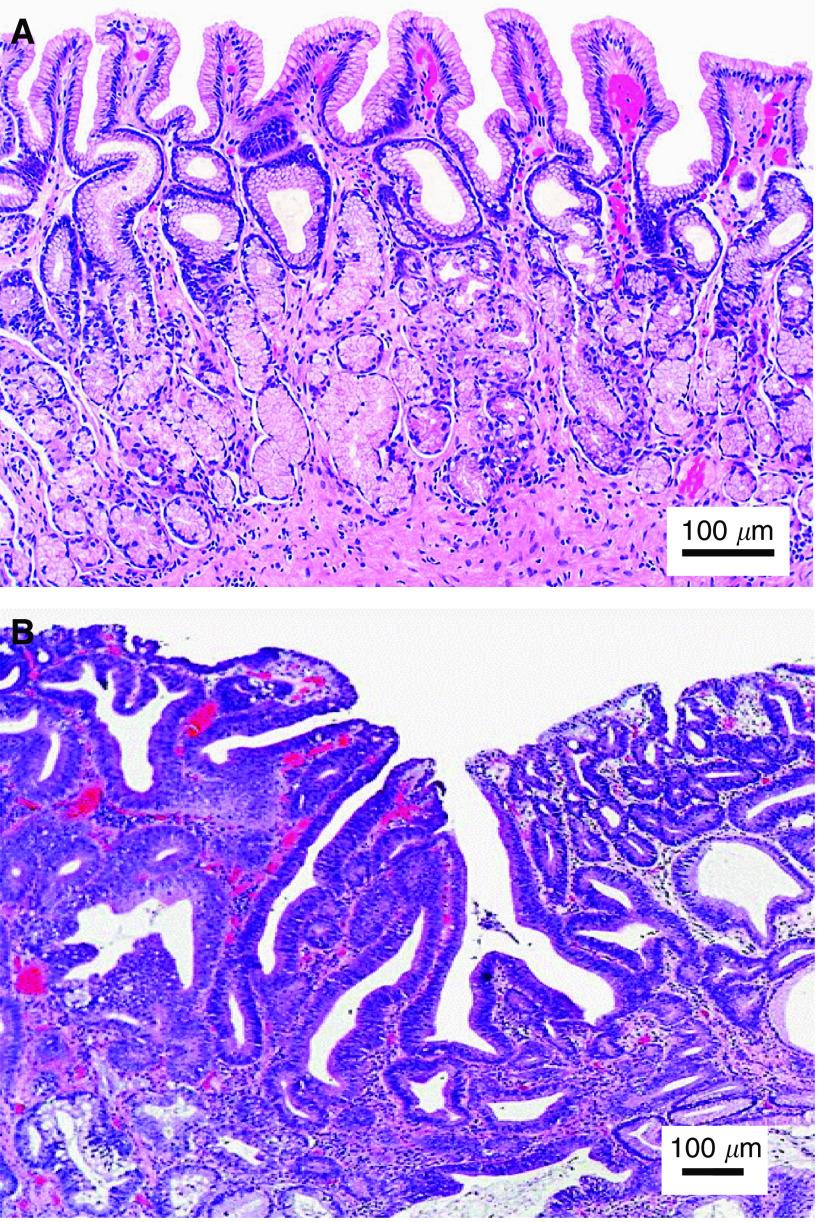

Raman spectroscopy is a molecular vibrational spectroscopic technique that is capable of optically probing the biomolecular changes associated with diseased transformation. The purpose of this study was to explore near-infrared (NIR) Raman spectroscopy for identifying dysplasia from normal gastric mucosa tissue. A rapid-acquisition dispersive-type NIR Raman system was utilised for tissue Raman spectroscopic measurements at 785 nm laser excitation. A total of 76 gastric tissue samples obtained from 44 patients who underwent endoscopy investigation or gastrectomy operation were used in this study. The histopathological examinations showed that 55 tissue specimens were normal and 21 were dysplasia. Both the empirical approach and multivariate statistical techniques, including principal components analysis (PCA), and linear discriminant analysis (LDA), together with the leave-one-sample-out cross-validation method, were employed to develop effective diagnostic algorithms for classification of Raman spectra between normal and dysplastic gastric tissues. High-quality Raman spectra in the range of 800-1800 cm(-1) can be acquired from gastric tissue within 5 s. There are specific spectral differences in Raman spectra between normal and dysplasia tissue, particularly in the spectral ranges of 1200-1500 cm(-1) and 1600-1800 cm(-1), which contained signals related to amide III and amide I of proteins, CH(3)CH(2) twisting of proteins/nucleic acids, and the C=C stretching mode of phospholipids, respectively. The empirical diagnostic algorithm based on the ratio of the Raman peak intensity at 875 cm(-1) to the peak intensity at 1450 cm(-1) gave the diagnostic sensitivity of 85.7% and specificity of 80.0%, whereas the diagnostic algorithms based on PCA-LDA yielded the diagnostic sensitivity of 95.2% and specificity 90.9% for separating dysplasia from normal gastric tissue. Receiver operating characteristic (ROC) curves further confirmed that the most effective diagnostic algorithm can be derived from the PCA-LDA technique. Therefore, NIR Raman spectroscopy in conjunction with multivariate statistical technique has potential for rapid diagnosis of dysplasia in the stomach based on the optical evaluation of spectral features of biomolecules.